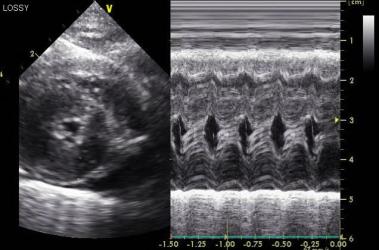

Ekokardiyografi

Kalp hastalıklarında tanının en kıymetli araçlarından biri kuşkusuz ki ekokardiyografi ile kalbin iç yapıları, duvar kalınlıkları ve kapak hareketleri ile çevre dokuları hakkında detaylı görüntüler alabilmek; kan akım dinamiklerini incelemektir. Bu amaçla özel problu ve yazılımlı ultrasonografi cihazları ile hastalarda herhangi bir yatıştırıcı yada anestesi uygulamadan yarım saat gibi kısa bir sürede muyaenelerini gerçekleştiriyoruz. Elde edilen sonuçları her ırk ve vücut ağırlığına uygun referans tablolarınca değerlendirerek hastalığın kesin tanısını oluşturuyoruz.